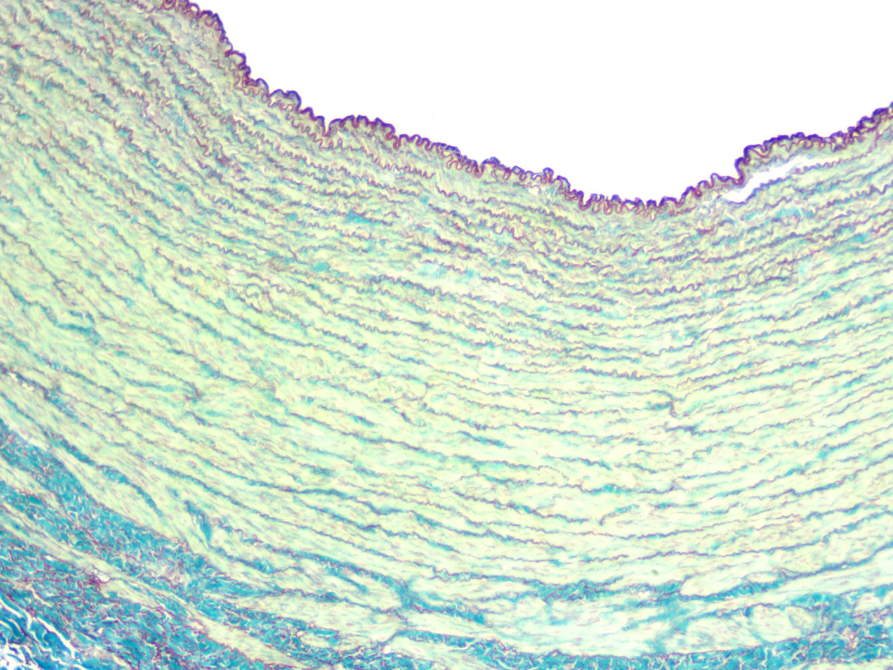

Arteria pulmonar (muscular)

la arteria más pequeña

Rodeado en verde - túnica adventicia desprendida

Túnica media - con fibras musculares lisas dispuestas helicoidalmente